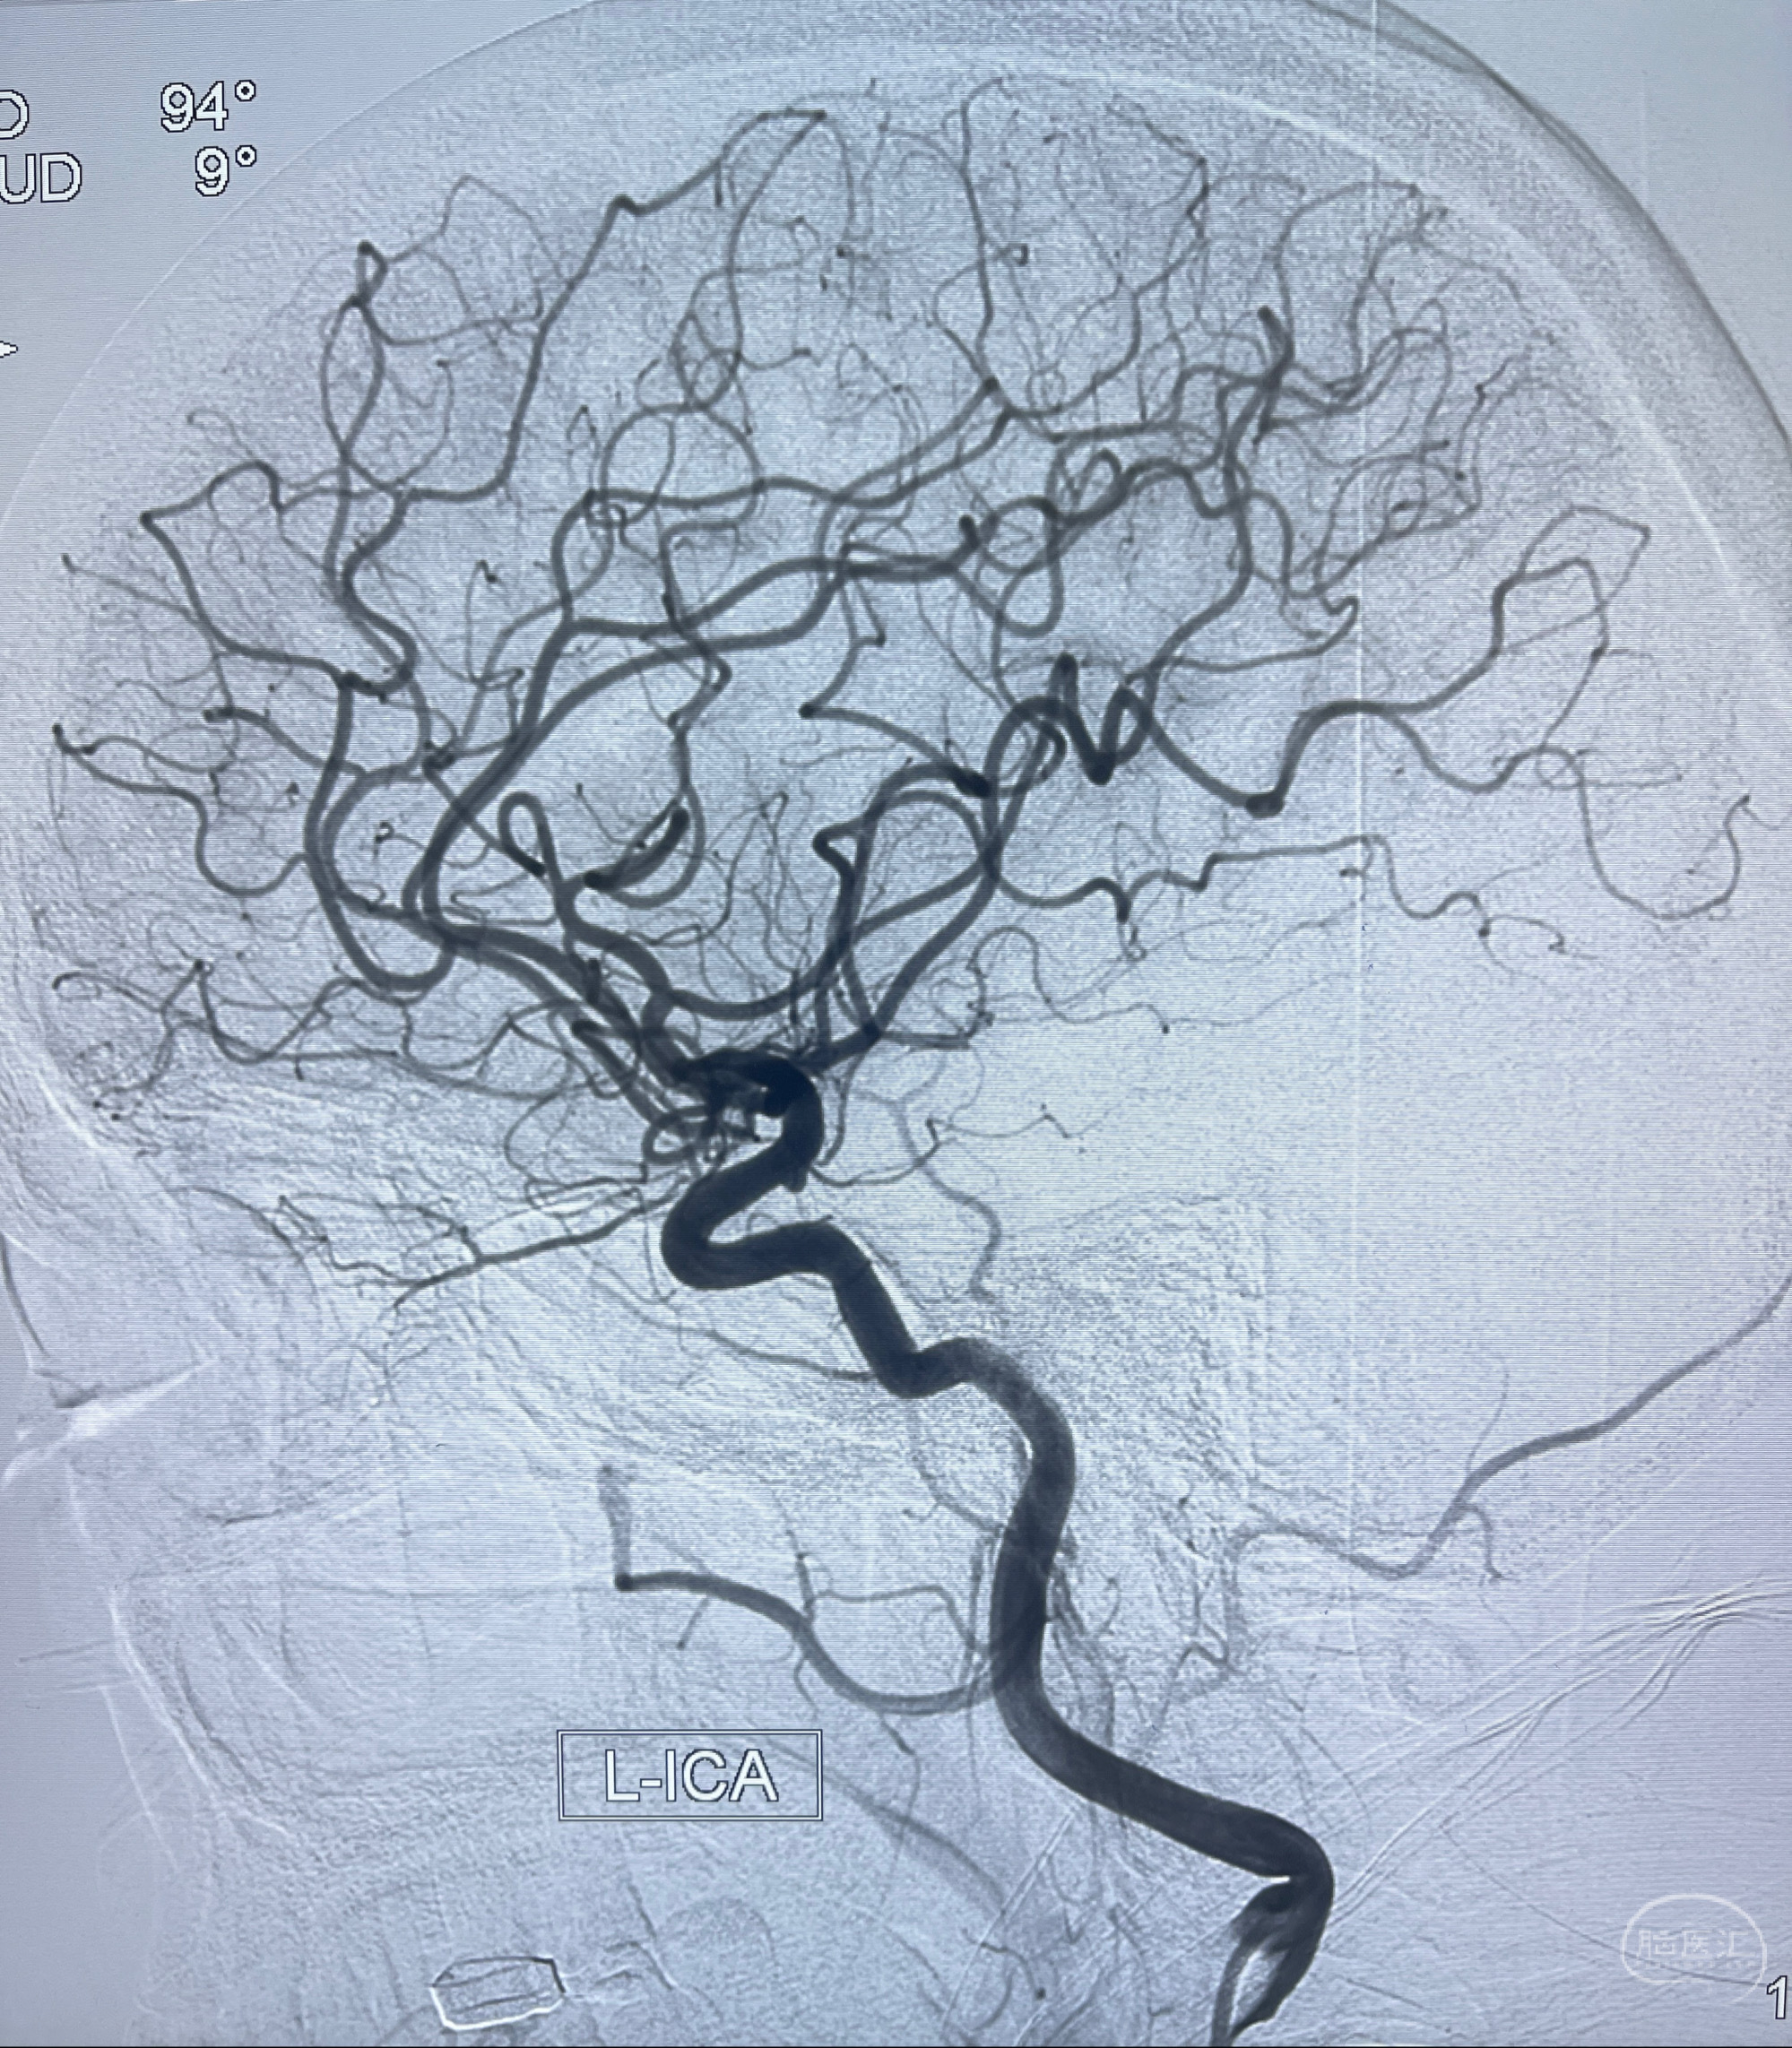

2023-02-02 沛县人民医院 头颅CTA:大脑动脉环发育变异,头颈部动脉粥样硬化,双侧颈内动脉及椎动脉颅内段多发狭窄;

2023-02-15DSA